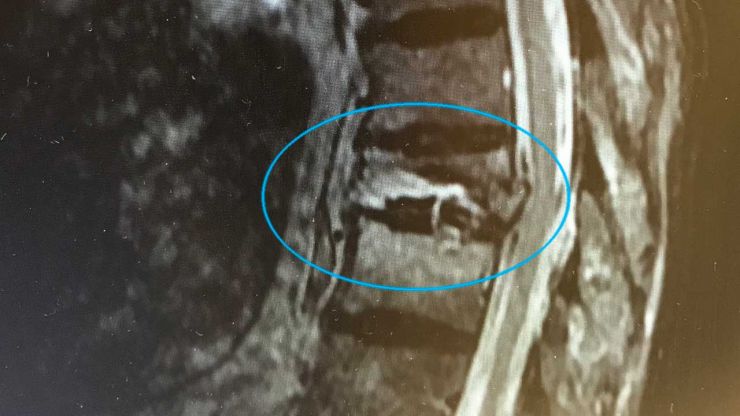

SpondyloIisthesis (spon-dill-oh-liss-thee-sis) is a fancy long term meaning one vertebra slips over another. Although this disease primarily effects the elderly as a degenerative disease, it may be congenital (present at birth) or discovered early in life.

Childhood spondylolisthesis can be caused when the pars articularis (par-z-are-tick-you-layer-es) does not fuse during early development. When these bony pieces do not grow together, a bony posterior weakness results in the vertebra

Spondylolisthesis may result after injury or dur ing overuse because the existing bony weakness lends the area susceptible to breakage. A physician whose speciality is the spine best deals with this condition.

Elderly spondylolisthesis may result when the stabilizing spinal structures begin to deteriorate. This occurs particularly in the lower back, which is responsible for carrying most of the body's weight.

Sometimes the spinal joints become arthritic and wear out, which may create spinal instability. As verte brae lose their normal alignment, one vertebra might actually slip forward over the one below.

When a vertebra slips forward, the neuroforamen (window), where the nerves exit the spinal canal, may become closed causing nerve compression and sciatica. This condition is similar to spinal stenosis.

In a few instances conservative measures fail. Depending on the patient's symptoms, a surgical pro cedure termed a laminectomy (lamb-in-eck-toe-me, removal of bone) combined with spinal fusion may be necessary. Spinal fusion stabilizes the affected area(s) of the spine using hardware (rods, screws, plates) and bone grafting.